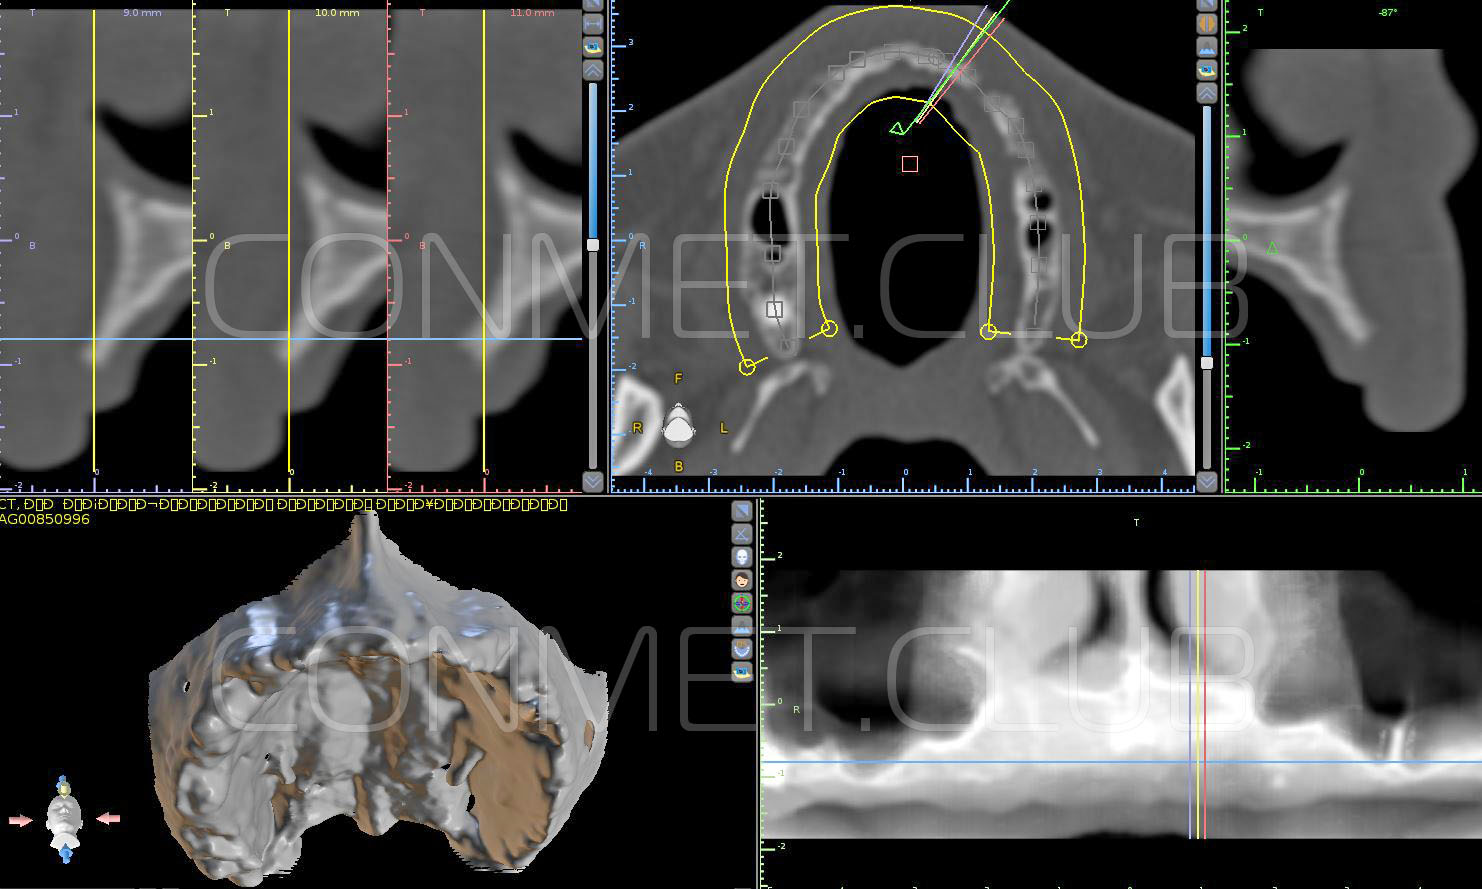

1. Пациенту было произведено МСКТ исследование нижней челюсти, с последующим созданием STL модели. В зуботехнической лаборатории был изготовлен восковой шаблон с искусственными зубами с учетом индивидуальных прикусных взаимоотношений (пока это делает зубной техник точно так же, как при изготовлении съемного пластиночного протеза).

2. После этого произвели компьютерное моделирование самого имплантата и фиксирующих элементов. Примечательно, что в абатментах, использовался отлично зарекомендовавший себя и проверенный десятилетиями интерфейс КОНМЕТ! В результате получили несколько специальных файлов, позволяющих не только сделать сам имлантат, но еще до операции изготовить и сами зубы. Данные файлы передали в изготовление на специальном 3D оборудовании.

Посмотрите на небольшом клиническом примере новый подход к конструированию имплантата по сравнению с имплантатами описанными в начале этой статьи.